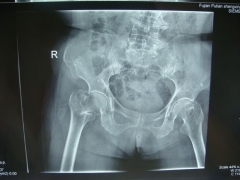

7月9日,莆田盛興醫(yī)院為一名89歲的女性髖部骨折患者順利實施了手術。   數(shù)日前,東……

近日,平海鎮(zhèn)90歲高齡的周阿婆即將出院。她感慨地對筆者說:“真沒想到我還能下床走路……